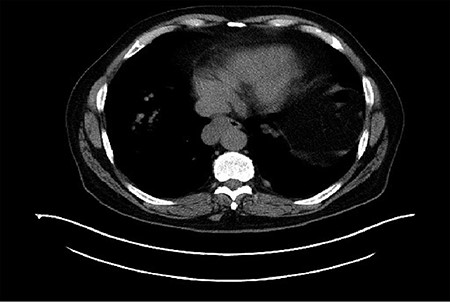

The patient is a 67-year-old male with a history of atrial fibrillation and hyperlipidemia who presented with several months of dysphagia to solids. The endoscopic evaluation revealed a ~4 × 2.3 cm submucosal lesion arising from the muscularis propria in the distal esophagus (Fig. 1). The lesion was 2 cm proximal to the GE junction and intermittently disappearing with peristaltic contractions. The lesion was biopsied and showed low-grade GIST with 1–3 mitoses per high power field and was CD 117 positive. Computerized tomography (CT) scan showed a right esophageal mass without evidence of local invasion (Fig. 2).

Computerized tomography (CT) demonstrated a right distal esophageal mass.